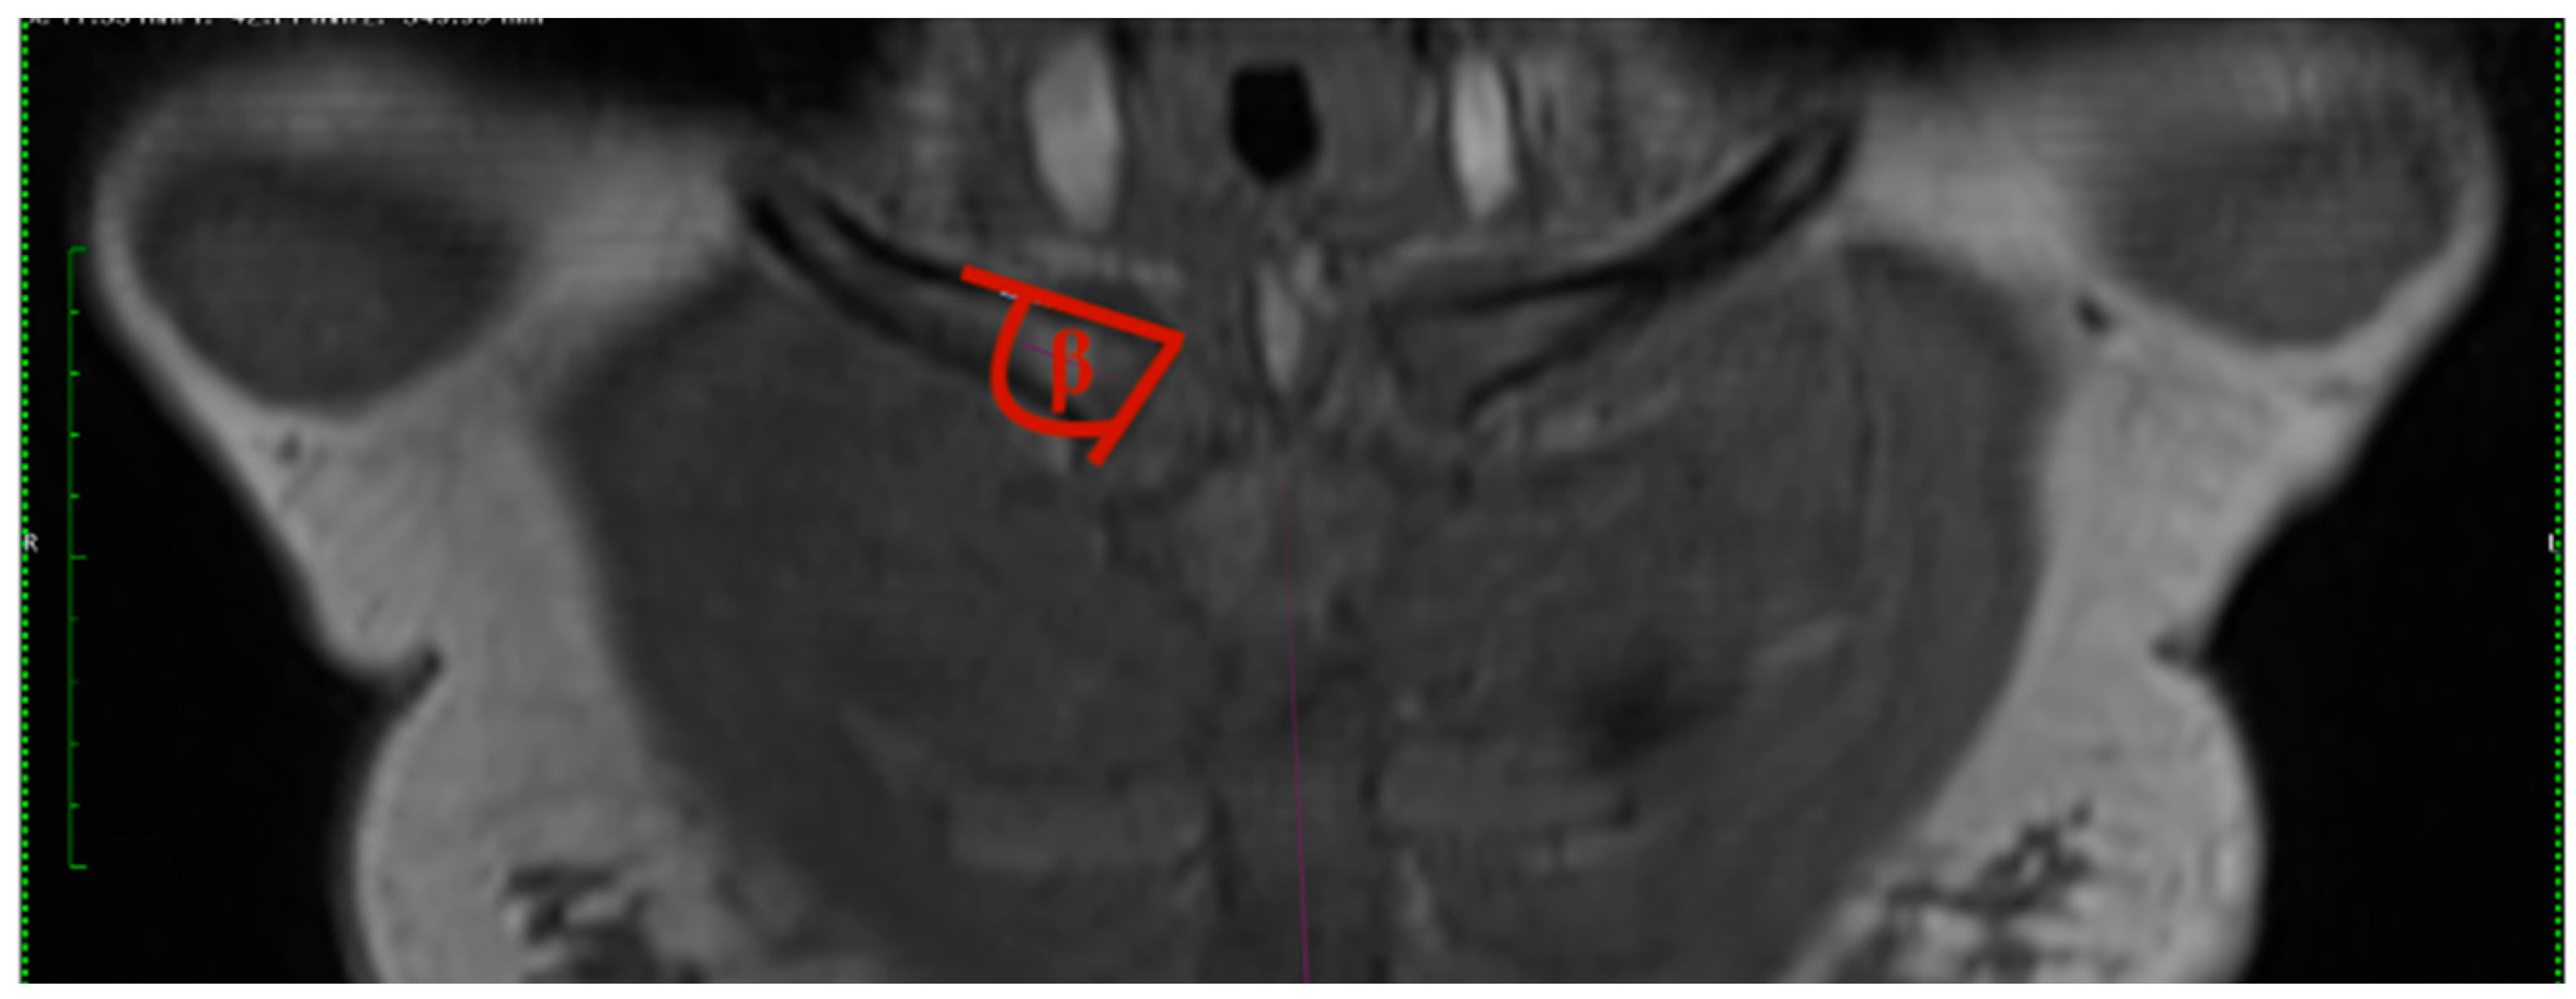

- Clavicular angle: The clavicular angle was measured by the plug-in after two tangents were drawn. One aligns at the articular surface of the clavicular end of the sternoclavicular joint, and the other one at the cranial border of the medial end of the clavicle (Figure 2).